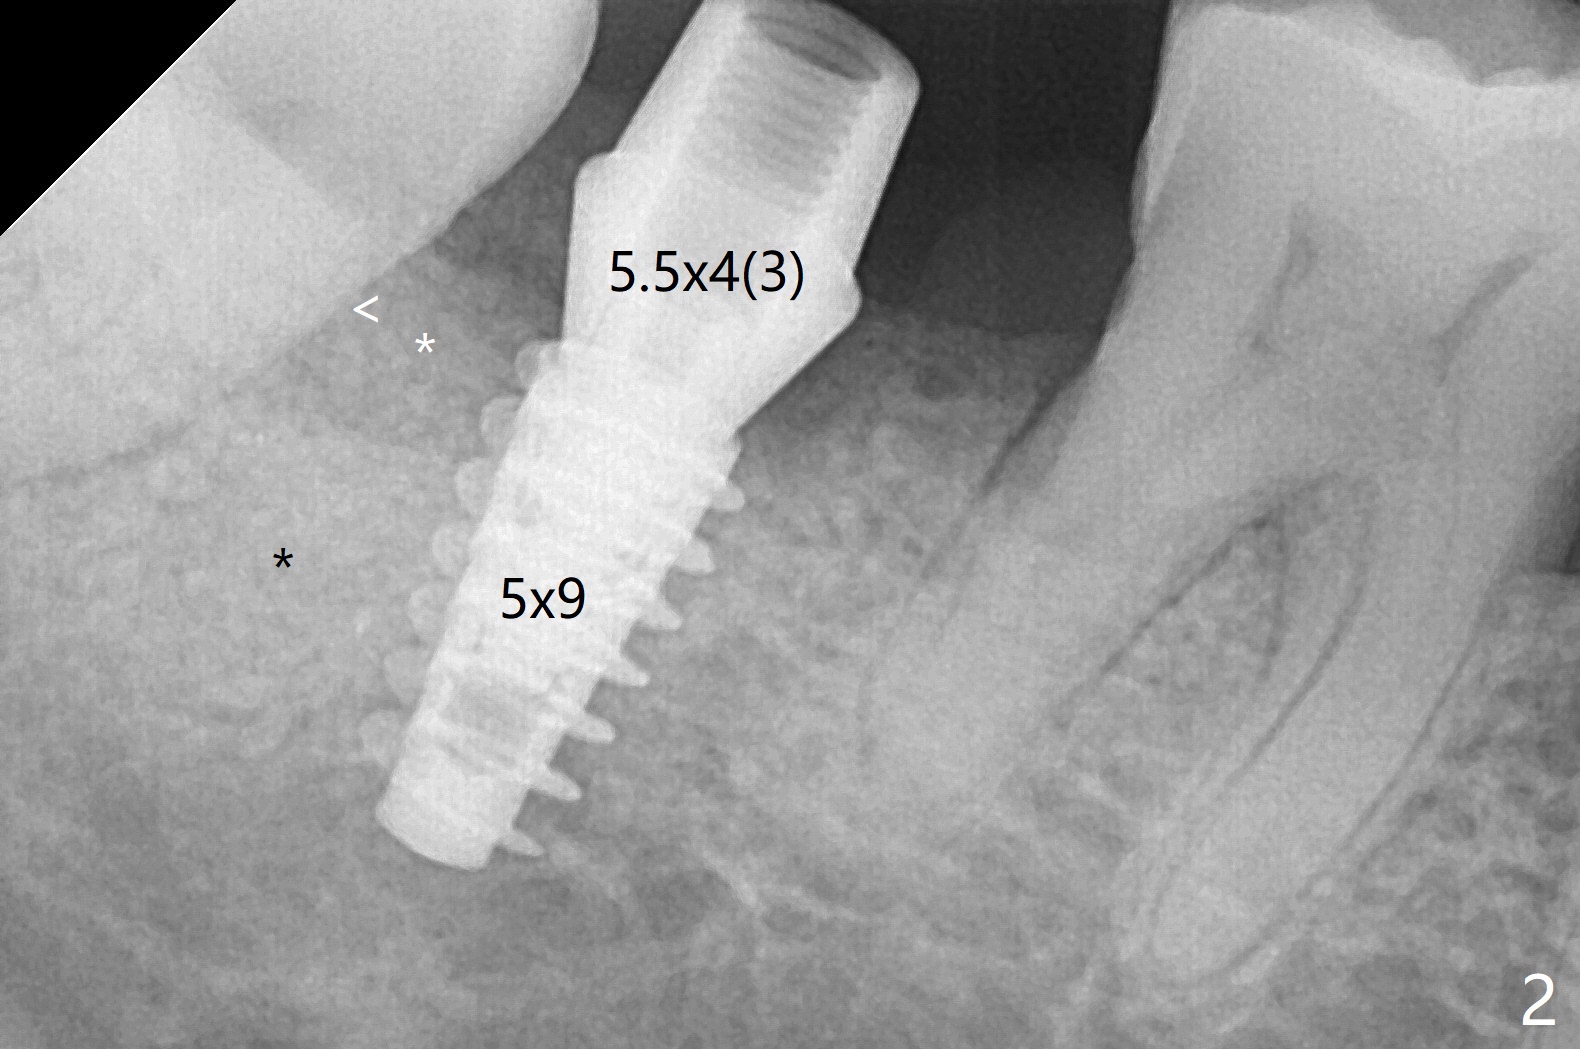

右下7有两个融合牙根,很长,起初(拔除后)有点害怕初步稳定性,使用导板完成近中窝4x10毫米钻洞后,植入4.5x10毫米报废植体,当时没有发觉植体已经发生远中偏移(图一:箭头,因为近中牙槽嵴高(*),而中隔缺失)。当正式植体植入后(图二),病人发现偏移,术者觉得临床上还可以,以为可能因为X光拍摄角度问题。再次放入粘性骨粉后,咬翼片拍摄注意角度问题,但是偏移仍存在(图三)。为了防止偏移现象,要么设计时有意往阻力大的地方偏移少许(例如这个病例1毫米,图四),要么发现偏移后,有意使用侧方切割钻头(Lindamann bur)去除阻力(近中骨)。如果扭力低,包埋植体。术后一个月取出临时牙冠,骨粉仿佛成为牙龈一部分(图五:*),之后暂时粘固粉固定牙冠。术后五个月骨粉好像与邻牙牙根和植体愈合(图六:*)。永久性粘固后,基台螺丝拧紧20Ncm。